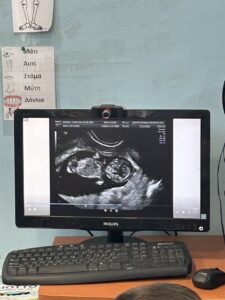

Η δραστηριότητα αυτή έχει ως στόχο να γνωρίσουν τα παιδιά τη διαδικασία του υπερηχογραφήματος και να κατανοήσουν πώς οι γιατροί χρησιμοποιούν αυτή την τεχνολογία για να δουν το μωρό μέσα στην κοιλιά της μαμάς. Μέσα από την παρακολούθηση μιας εικόνας υπερήχου στον υπολογιστή, τα παιδιά παρατηρούν και αναγνωρίζουν τα βασικά σημεία του σώματος του μωρού, δίνοντας έμφαση στα οστά που είναι ορατά.

- Τα παιδιά παρακολουθούν στον υπολογιστή μια εικόνα υπερήχου που δείχνει το μωρό μέσα στη μήτρα.

- Στη συνέχεια, γίνεται εξήγηση για το τι είναι ο υπέρηχος και πώς μας βοηθά να βλέπουμε τα οστά και τα μέρη του σώματος του μωρού.